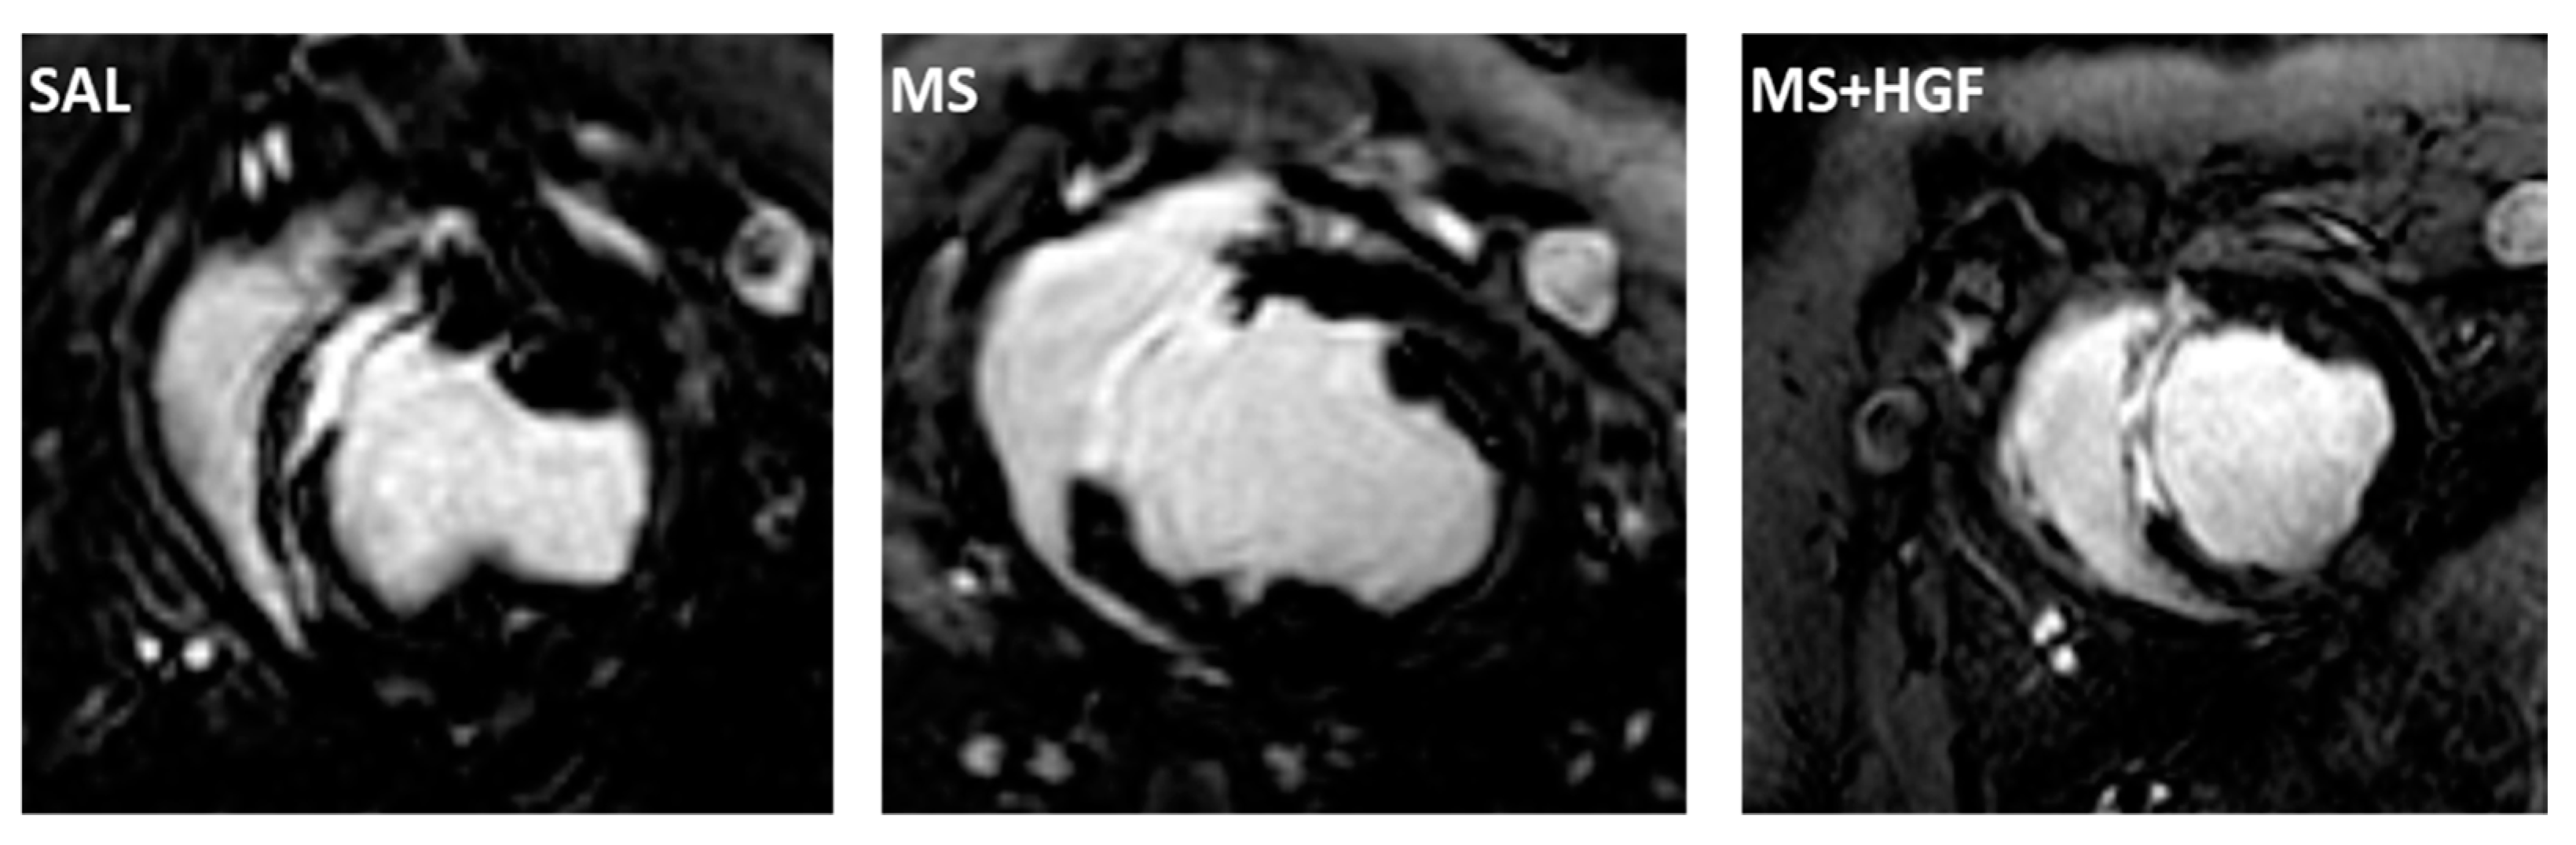

3.3. cMR

| cMR Parameter | SAL | MS | MS+HGF |

|---|---|---|---|

| %MI cMR1 | 20 ± 8 a | 20 ± 5 | 19 ± 3 a |

| %MI cMR2 | 9 ± 4 a | 9 ± 3 | 11 ± 2 a |

| ∆MI (%) | −11 ± 6 | −15 ± 7 | −9 ± 4 |

| EF (%) cMR1 | 26 ± 9 a | 26 ± 5 | 24 ± 8 a |

| EF (%) cMR2 | 36 ± 8 a | 32 ± 10 | 31 ± 5 a |

| ∆EF (%) | 10 ± 9 | 6 ±9 | 7 ±7 |

| EDVi (mL/m2) cMR1 | 68 ± 16 | 68 ± 10 | 80 ± 14 |

| EDVi (mL/m2) cMR2 | 86 ± 22 | 74 ± 13 | 89 ± 16 |

| ∆EDVi (mL/m2) | 18 ± 27 | 7 ±13 | 9 ± 19 |

| ESVi (mL/m2) cMR1 | 51 ± 17 | 51 ± 9 | 62 ± 15 |

| ESVi (mL/m2) cMR2 | 56 ± 21 | 51 ± 12 | 62 ± 14 |

| ∆ESVi (mL/m2) | 5 ± 26 | 1 ± 11 | 0.5 ± 18 |